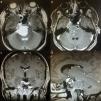

Los condromas craneales son tumores derivados de remanentes de células embrionarias condrocíticas que habitualmente aparecen en la sincondrosis de la base del cráneo. A diferencia del resto del organismo,donde los tumores condroides constituyen el tumor óseo primario más frecuente solo por detrás de los de estirpe hematopoyética, a nivel craneal constituyen una entidad poco frecuente con una incidencia de menos del 1% de los tumores intracraneales. Presentamos el caso de un varón de 42años remitido a nuestra consulta por el hallazgo de una lesión extraaxial situada en la región del cavum de Meckel y extensión a la fosa posterior con compresión del troncoencéfalo tras clínica de paraparesia de 6meses de evolución. Bajo el diagnóstico de un neurinoma del V par craneal se realiza una exéresis subtotal del tumor mediante un abordaje combinado supra-infratentorial presigmoideo. El resultado anatomopatológico postoperatorio confirma el diagnóstico de condroma craneal.

Cranial chondromas are tumours arising from chondrocyte embryonic remnants cells that usually appear in the skull base synchondrosis. In contrast to the rest of the organism, where chondroid tumours are the most common primary bone tumour just behind the haematopoietic lineage ones, they are a rarity at cranial level, with an incidence of less than 1% of intracranial tumours. The case is reported on a 42 year-old male referred to our clinic due to the finding of an extra-axial lesion located close to the Meckel's cave region, with extension to the posterior fossa and brainstem compression after progressive paraparesis of 6 months onset. With the diagnosis of trigeminal schwannoma, a subtotal tumour resection was performed using a combined supra-infratentorial pre-sigmoidal approach. The postoperative histopathology report confirmed the diagnosis of cranial chondroma.